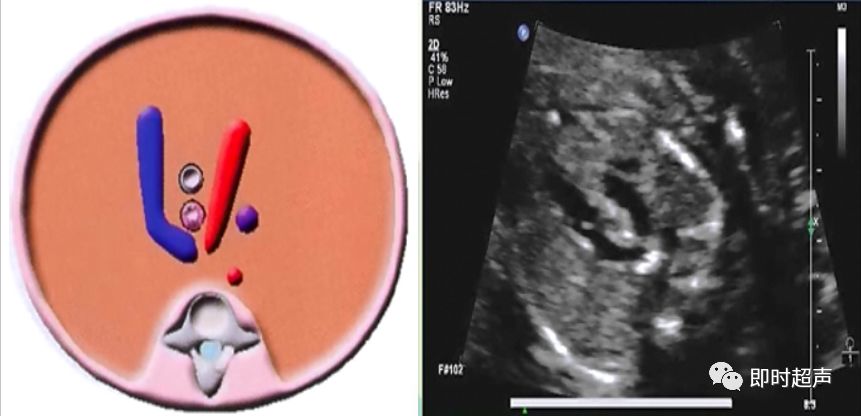

五、应用你自己的左手作心脏模型,当实际操作时可帮助你认别主肺动脉等大血管的方位:

左手做成折叠手:大拇指先向掌心折叠,它代表主肺动脉;食指弯曲压在大拇指上 ,它代表主动脉;中指伸直,它代表上腔静脉;近腕关节端的手背代表心尖。其它两指无任务,故让它们折叠着。

(当胎儿仰卧位,胎儿心尖指向外上项限,肺动脉在外上项限。如图示。

大拇指为主肺动脉PA;食指为主动脉;中指为上腔静脉。)

当胎儿右侧卧位,胎儿心尖指向内上项限,肺动脉在内上项限。如图示。

大拇指为主肺动脉PA;食指为主动脉;中指为上腔静脉。